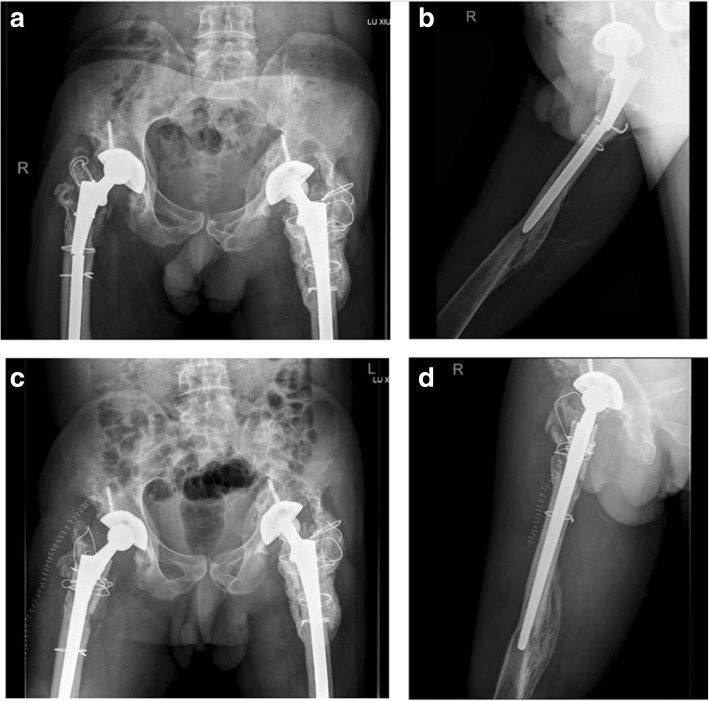

A 51-year-old male visited us complaining of right hip pain in June 2011. He had undergone bilateral THA more than 10 years prior. X-rays revealed wear of the acetabular linings of both hips, and severe osteolysis of the proximal femora and acetabula (Fig. 1a). Preoperative laboratory data revealed no sign of infection; we thus revised the right hip on June 24, 2011. During operation, we found that the acetabular cup was firmly fixed; we thus replaced the acetabular polyethylene lining and the alumina ceramic head. The femoral stem was loose so a DePuy Solution stem (diameter 12 mm) was placed after removing the old stem. The DePuy stem is a distally fixed, extensively porous-coated cylindrical revision femoral stem (Fig. 1b). We grafted alloallergic cancellated bone onto the acetabular side; we did not graft the proximal femoral bone defect. On April 11, 2013, we revised the left hip. Again, we found that the acetabular cup was firmly fixed and the femoral stem loose. We grafted alloallergic cancellated bone onto the acetabular side, replaced the acetabular polyethylene lining and the alumina ceramic head, and again used a DePuy Solution stem (diameter 12 mm) for femoral revision (Fig. 1c and d). However, on June 122,014, the patient returned to hospital complaining of left hip pain and an inability to move after changing his sitting posture. Blood tests revealed a normal erythrocyte sedimentation rate and a C-reactive protein level of 56.8 mg/L. A stem fracture was evident on X-rays (Fig. 2a and b). We revised the left hip 11 days later; the cup and acetabular polyethylene lining were satisfactory. We replaced the femoral head and used a 14-mm-diameter DePuy Solution stem to revise the femoral side. Allograft bone augmentation of the proximal femur followed by cerclage wiring was performed (Fig. 2c and d). However, the patient returned again in September 2017 with a right femoral prosthetic fracture (Fig. 3a and b). We replaced the femoral head and the acetabular polyethylene lining, and used a 14-mm-diameter Wagner SL stem (Zimmer, Warsaw, IN, USA) to revise the right hip. We performed allograft bone augmentation of the proximal femur followed by cerclage wiring (Fig. 3c and d).

Fig. 2.

a and b: Pre-operative AP radiographs taken in December 2014 showing the left femoral stem fracture. c and d: Radiographs taken after revision of the left hip

Fig. 3.

a and b: Pre-operative AP radiographs taken in September 2017 showing the right femoral stem fracture. c and d: Radiographs taken after revision of the right hip